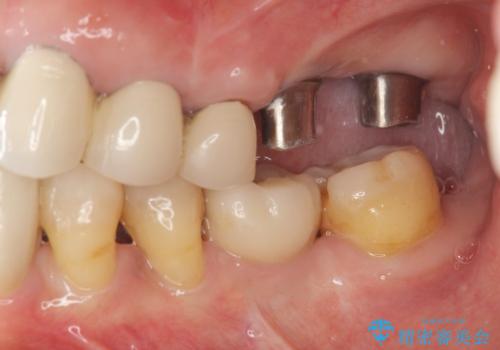

- 他院で治療した左上のセラミック部位の痛みを訴えて来院されました。

支台となる小臼歯に過大な負担のかかる遊離端ブリッジが装着されていたため、義歯かインプラントを用いた再補綴計画を提案しよりしっかりと噛めるインプラント治療をご希望されました。

親知らずを除く、一番後ろの歯を失った場合(第二大臼歯)ブリッジによる機能回復は支台となる歯の大きな負担となり将来的に歯をさらに失う原因の一つとなりえます。